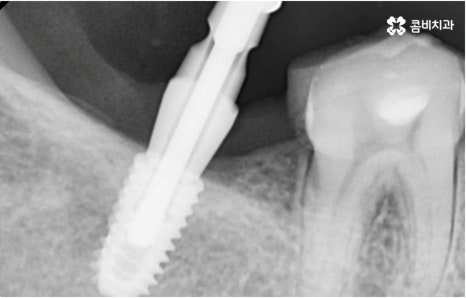

자연 치아를 살리기 위한 거의 마지막 단계의 보존 치료가 바로 신경치료, 재신경치료, 치근단절제술 등이며, 만약 치아재식술을 통해서도 살릴 수 없을 정도로 손상이 깊고 심하다면 해당 치아를 발치하고 임플란트를 통해 인공 치아로 대체해 줄 필요가 있습니다.

임플란트는 유치, 영구치 이후로 제 3의 치아라고 불리울 만큼 자연 치아의 상실에 대처하는 인공 치아 중에 가장 각광을 받고 있습니다. 저작력 회복이 80%에 가깝고 심미적으로 자신의 치아와 거의 다름없어 보이는 부분에서도 만족도가 높아 많은 분들이 찾고 있지만 식립 성공률과 안정적인 지속률에 크게 영향을 주는 올바른 위치 및 각도로의 식립을 무리하지 않게 진행하기 위해 술자의 높은 숙련도를 요하는 고난도의 수술이기 때문에 임상 경험이 많고 뛰어난 노하우를 갖추고 있는 담당의 선생님과 함께 하시는 것이 중요한 포인트라고 할 수 있어요.

환자분들의 상황에 따라 하루 만에 식립 및 임시 치아 장착까지 끝나서 바로 식사를 할 수 있는 원데이 임플란트 과정, 정밀 검사 후 디지털 장비를 이용하여 모의 수술 후 맞춤 가이드를 따라 무절개 / 최소절개 수술을 진행하는 네비게이션 임플란트 과정 등 관련 기술이 점점 더 섬세하게 발달하고 있어서 보다 편안한 이용이 가능하게 된 것은 사실이지만 본래 자신의 치아보다 좋은 인공 치아는 없을 것이기 때문에 건강할 때 이를 잘 유지 관리하고 구강 질환이 발생했을 때는 되도록 빠르게 이에 대처하실 필요가 있어요.